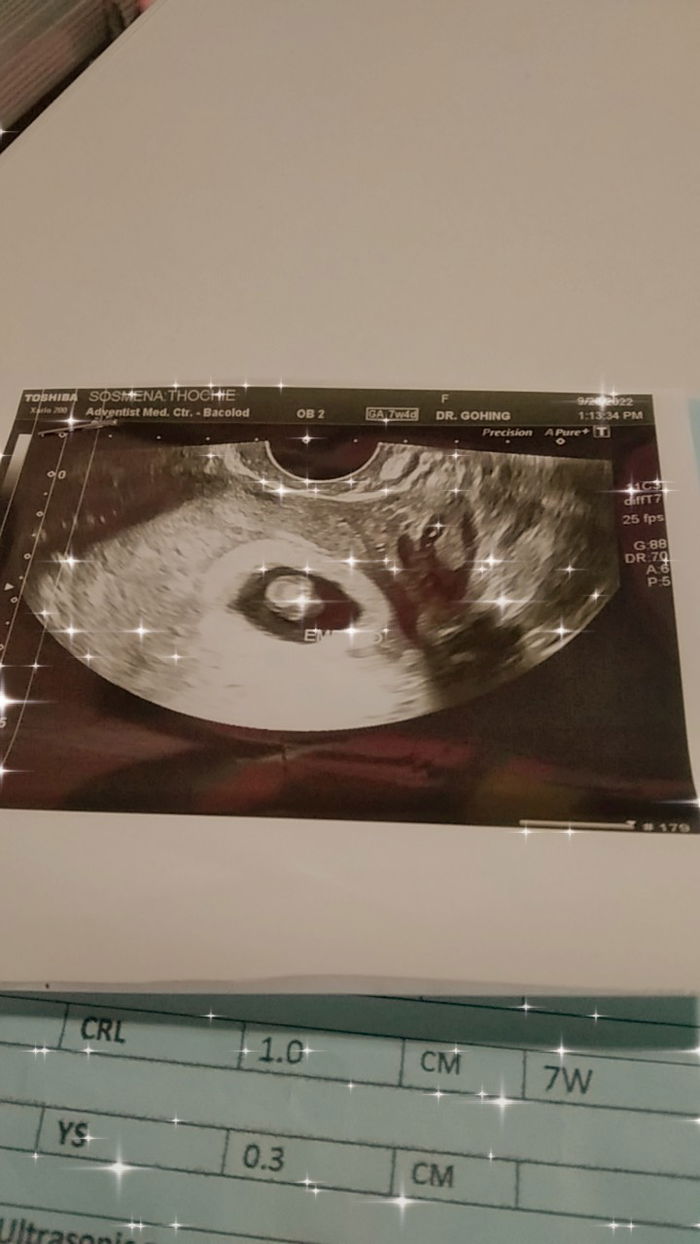

Based on my LMP my baby is about 5 weeks. I was advise to have a scan after 2 weeks. Omg!there was a heart beat. I cried when the doctor showed me the screen pointing on the tiny wing like structure that beats. My baby is alive this time.